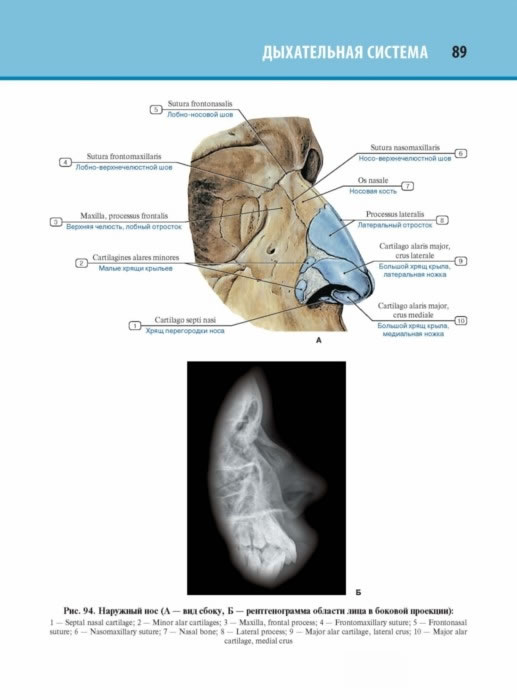

Карманный формат атласа удобен для ежедневного изучения анатомии. Уникальная концепция издания сформирована на основе иллюстрированного учебника «Анатомия человека» под редакцией академика РАН Л.Л. Колесникова и обширного опыта подготовки анатомических атласов издательством «ГЭОТАР- Медиа». В данном издании полностью переработан иллюстративный материал, добавлены новые изображения, схемы, материалы по рентгеноанатомии. Во втором томе представлена подробная информация о строении внутренних органов (пищеварительной, дыхательной, мочевой, половой, эндокринной, сердечно-сосудистой и лимфоидной систем).